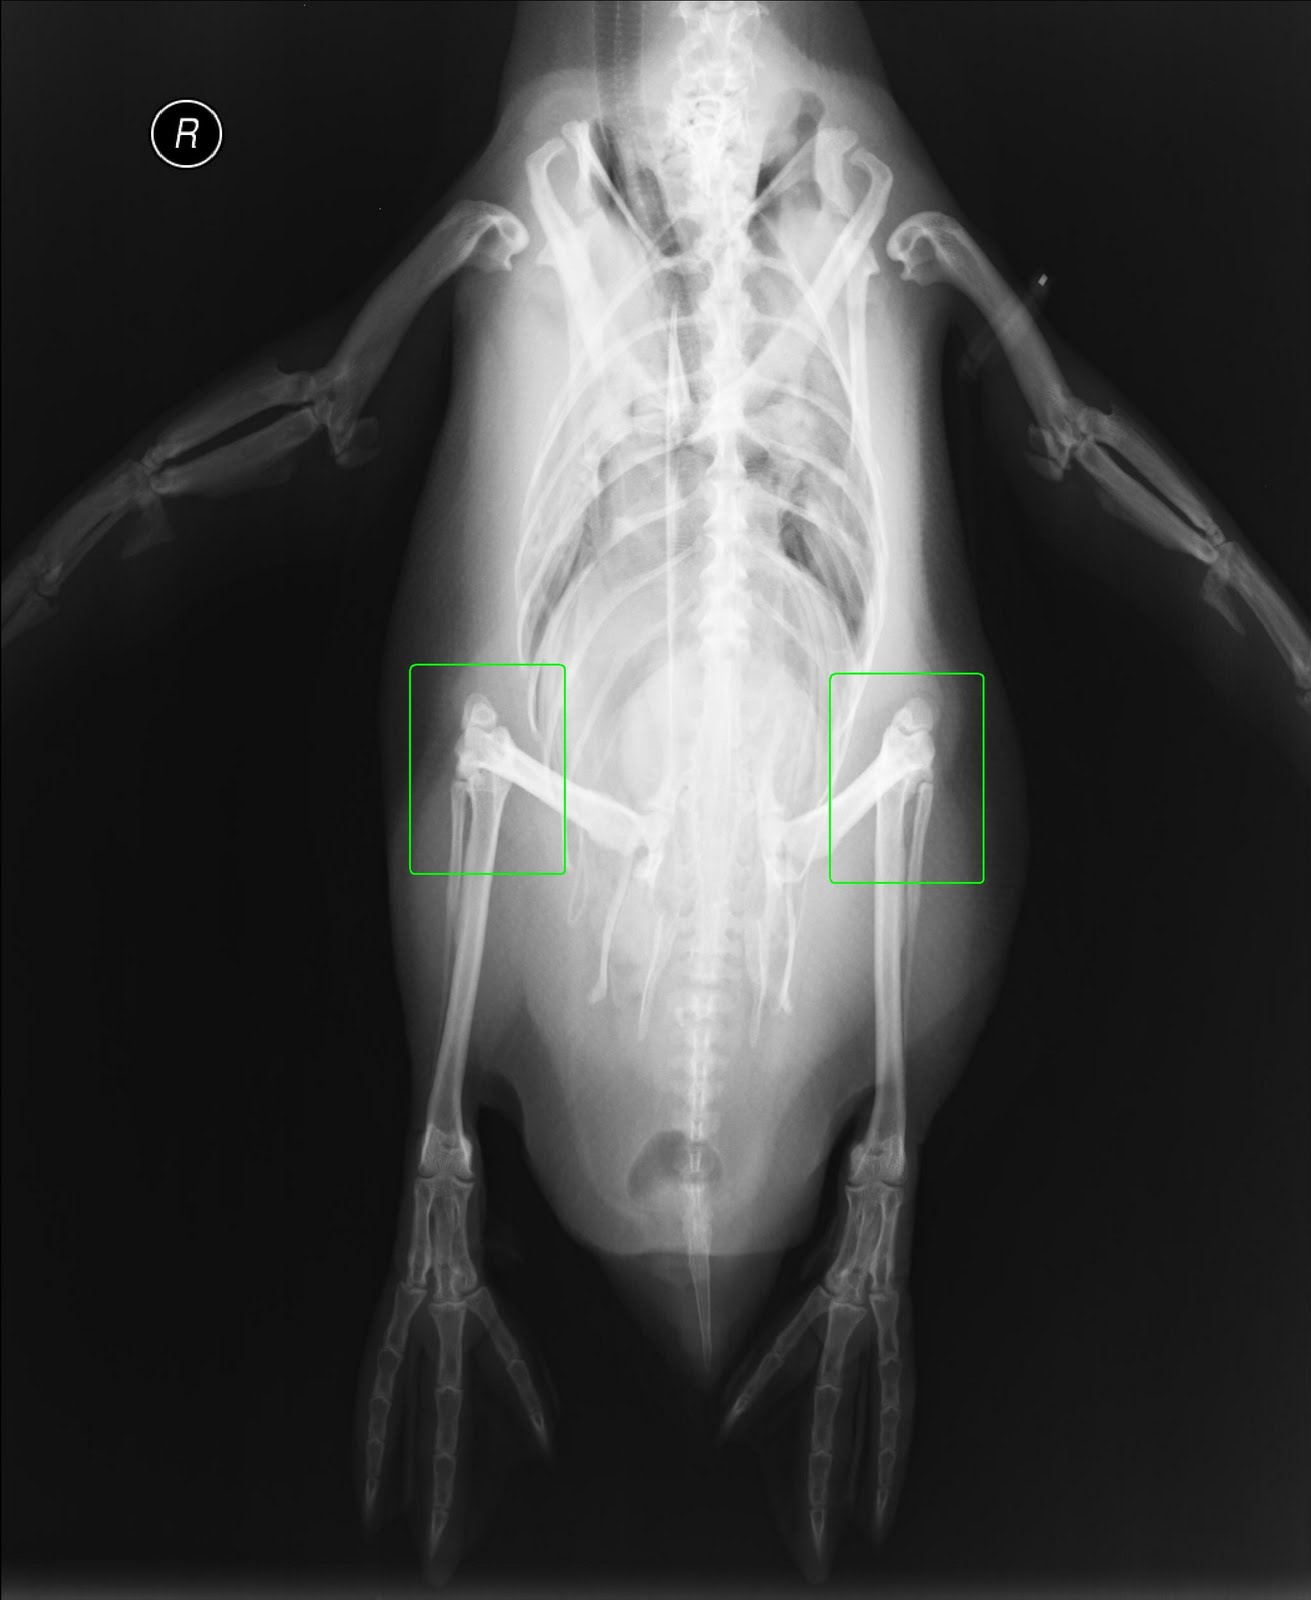

Do penguins have knees?

In short, the answer is yes, they do. Actually, a penguin’s leg is not much different from our own. They have a femur, a tibia, a fibula, and (of course) knees. Penguins also actually have much longer legs than they appear too. The upper leg is covered by feathers because, well, if you lived in the Arctic, I’m pretty sure you’d want your thighs covered as well.